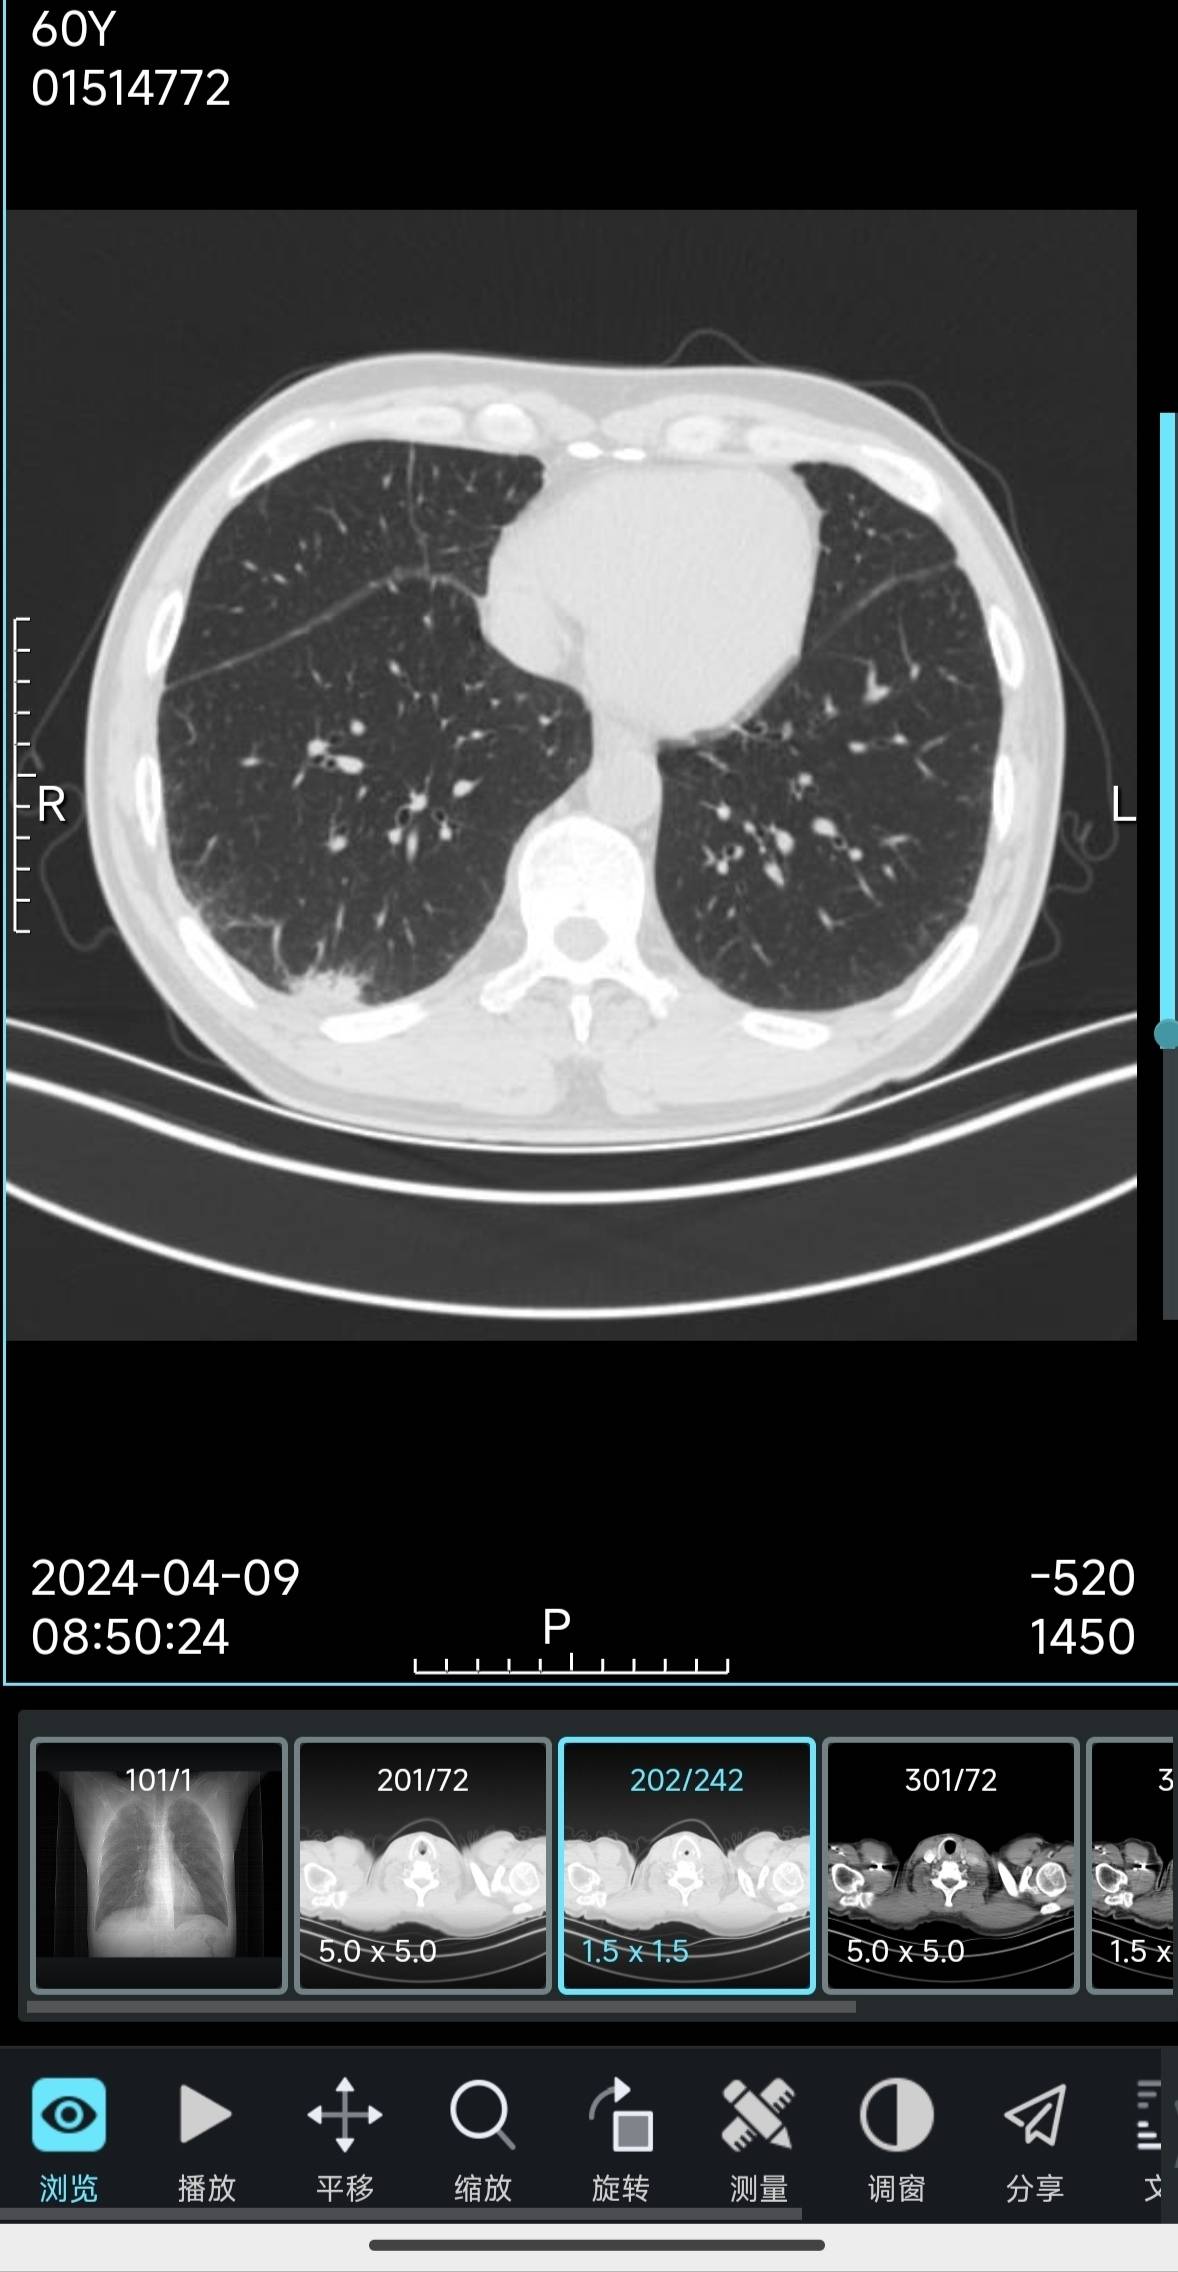

今天结果都出来了,腹盆ct跟之前一样,没有什么问题,但是胸部增强ct的结果跟之前有了变化,原来右肺下叶的实性结节被多发斑片状浸润影掩盖了,右肺门及纵隔多发肿大淋巴结,部分较前稍大,这个情况个人估计是比之前变差了。

我自己也在学着看ct影像,这次的图像确实跟之前的几次明显不一样,以前是一块比较明显的灰色,现在变成了一大片比较浅的灰色,应该是肿瘤开始侵犯其他部位,变差了的意思吧。

最近半年没有发帖,主要是我爸情况还比较稳定,每次ct结果也没有什么变化。这次他身体上也有变化,检查结果也有变化,不知道是不是已经到了耐药期了。